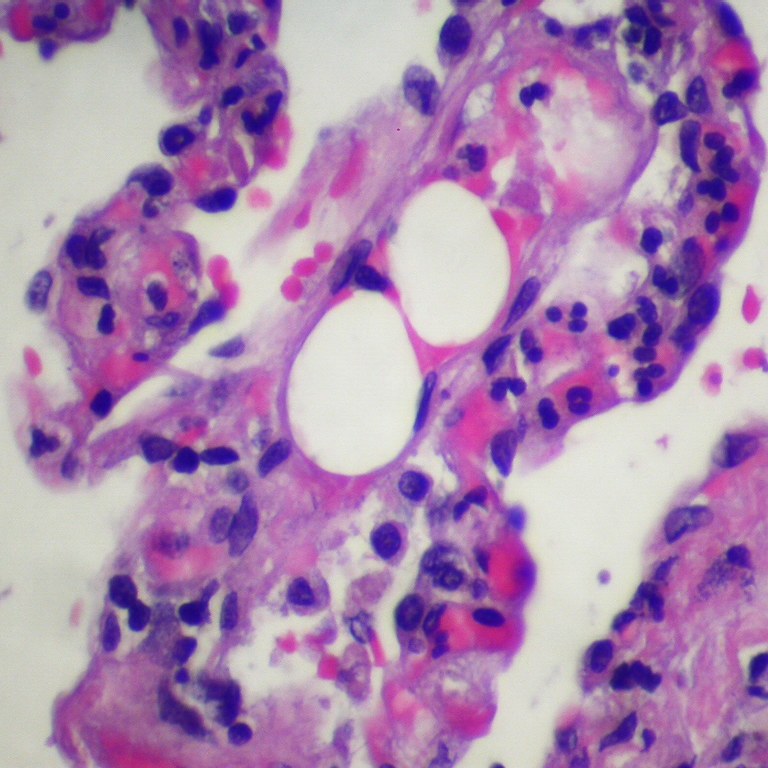

- “Fat embolism” by Pulmonary Pathology is licensed under CC BY-SA 2.0